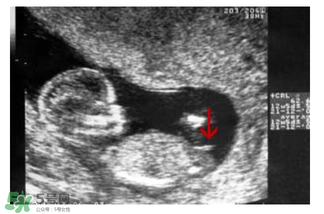

b超怎么看胎兒性別之看胎囊數(shù)據(jù)

胎囊也叫孕囊,胎囊只在懷孕早期見(jiàn)到。月經(jīng)28~30天規(guī)則來(lái)潮的婦女,停經(jīng)35天,B超就可以在宮腔內(nèi)看到胎囊。